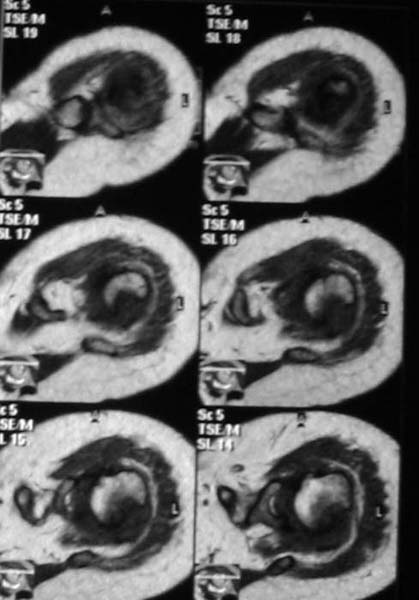

Активное отведение 80 гр., при пальпации - головка плечевой кости безболезненно вправляется и тут же самостоятельно вывихивается. Наложена косыночная иммобилизация, рентгенография (r3) и МРТ.В нашем диагностическом центре МРТ исследование плечевого сустава выполнено впервые, опыта у нас маловато :(.Вопросы: уточнение диагноза? какие исследования провести? тактика лечения?

МРТ1МРТ2МРТ3МРТ4

Из того, что видно на недостаточно качественно отсканированных МРТ - нижний подвывих плеча и синовиит. Непонятный очаг по заднему контуру головки плеча (то ли артефакт, то ли косой срез, проходящий между головкой и большим бугорком). Сухожилия вращательной манжетки выглядят целыми. Неправильная форма нижней части labrum glenoidale - разрыв ?

МРТ должен показать разрыв манжетки, но признаться я не большой эксперт по чтению МРТ сканов, хотя затемнение, отек мягких тканей по задней поверхности плеча видны Обычные рентгенограммы демонстрируют остеолизис в области большого бугорка.

1. На рентгене - нижний подвывих плеча и очаг остеолиза суставного бугорка с четкими контурами (вдавленный перелом на фоне остеопороза ? доброкачественная опухоль? аваскулярный некроз ? (хотя ни разу не слышал об аваскулярном некрозе плеча..)

2.выраженный выпот в полости сустава

Судя по снимкам, речь идTт о типичном случае Hill-Sachs Lesion. По этому поводу я позволю себе некоторый экскурс:

97 % всех вывихов плеча происходит по механизму комбинации отведения, разгибания и наружной ротации (А. Гринспан). В момент вывиха головка плеча ударяет о нижний край гленоида, что ведет к вдавленному или компрессионному перелому одной или обеих структур. Чаще всего, однако, повреждение возникает в задней латеральной области головки плечевой кости на переходе от головки к шейке. Этот диагноз можно выставить на основании рентгеновского снимка в переднезадней проекции с внутренней ротацией плеча. Несколько реже видно повреждение гленоида о передненижний перелом края. То, что мы называем Bankart Lesion. Это повреждение видно на ре. снимке в п.з. проекции при нейтральной позиции плеча. Разумеется хрящевые и мягкотканные повреждения (в смысле Банкарт) мы увидим лучше всего на ЯМР.

Учитывая описанную клинику, речь идTт о комбинации патологии. К сожалению, учитывая качество снимков NMR, я не могу провести достаточно точную верификацию состояния нижнего края гленоида, что впрочем, не меняет рекомендации. Для определения состояния РМ и дополнить исследование УЗИ мягких тканей плеча. В опытных руках достаточно информативное и дешевое исследование.